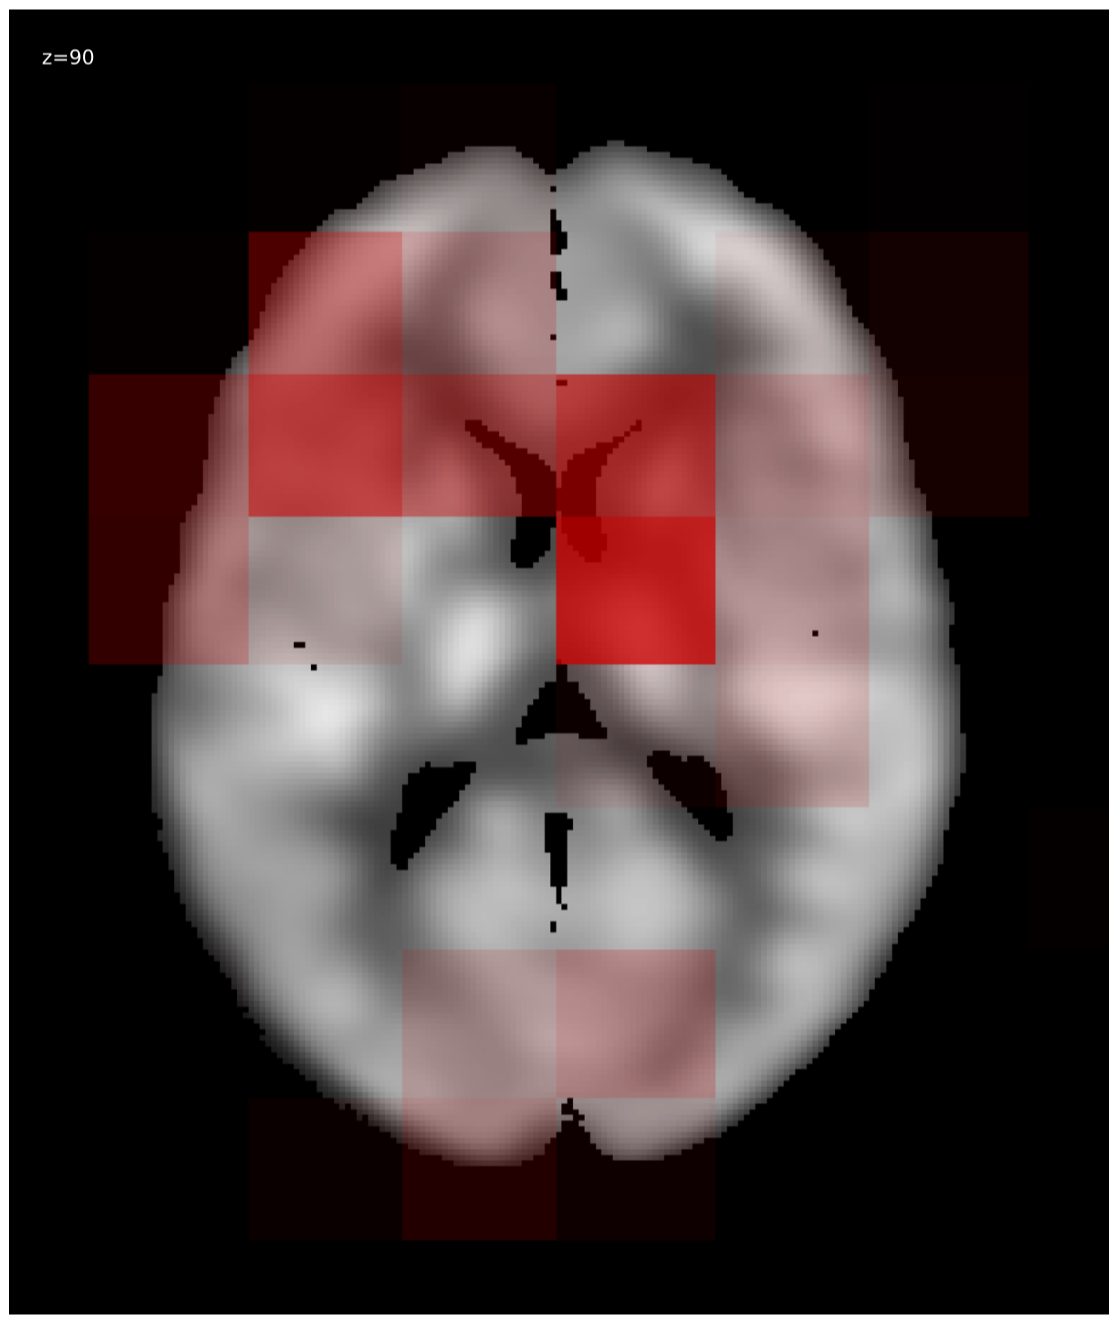

We generated relevance heatmaps for all visualizations methods, averaged over AD PET images in the test dataset. Figure 2 presents the visual comparison of these five methods. The red areas/dots indicate that regions were important for the decision making of the 3D-CNN model. From the result, we can see that all the visualization focuses mostly on similar brain regions. There are some differences, such as the heatmaps generated for the gradient-based methods are distributed. The heatmaps highlight the areas that the CNN network is most susceptible. For the LRP method, the heatmap shows the average relevance of each voxel for contributing to the AD diagnosis score. The heatmaps generated by the occlusion based methods are more focused on the specific regions and cannot administer with large areas of distributed relevance. The reason behind the issue is the occlusion path was not able to cover those areas (for example, the cortex) completely. Brain area occlusion presents very high relevance for the temporal lobe. Since in this method, only one area is covered at a time, that can cause such high importance for one region and minimal relevance for other regions.